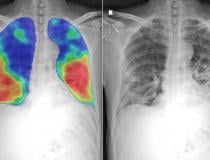

This photo gallery shows the variety of radiological presentations of COVID-19 (SARS-CoV-2) in medical imaging, including computed tomography (CT), radiograph X-rays, ultrasound, echocardiograms and magnetic resonance imaging (MRI). The radiology images show examples of typical COVID pneumonia in the lungs and the numerous complications the virus causes in the body in multiple organs, including the brain, kidneys, heart, abdomen and vascular system.

Ultrasound, especially hand-held ultrasound imaging devices, have become a primary imaging modality for novel coronavirus because of the ease to bag the device and sterilize it after use. CT and mobile X-ray systems are also used as front-line imaging systems for COVID-positive or suspected COVID patients.